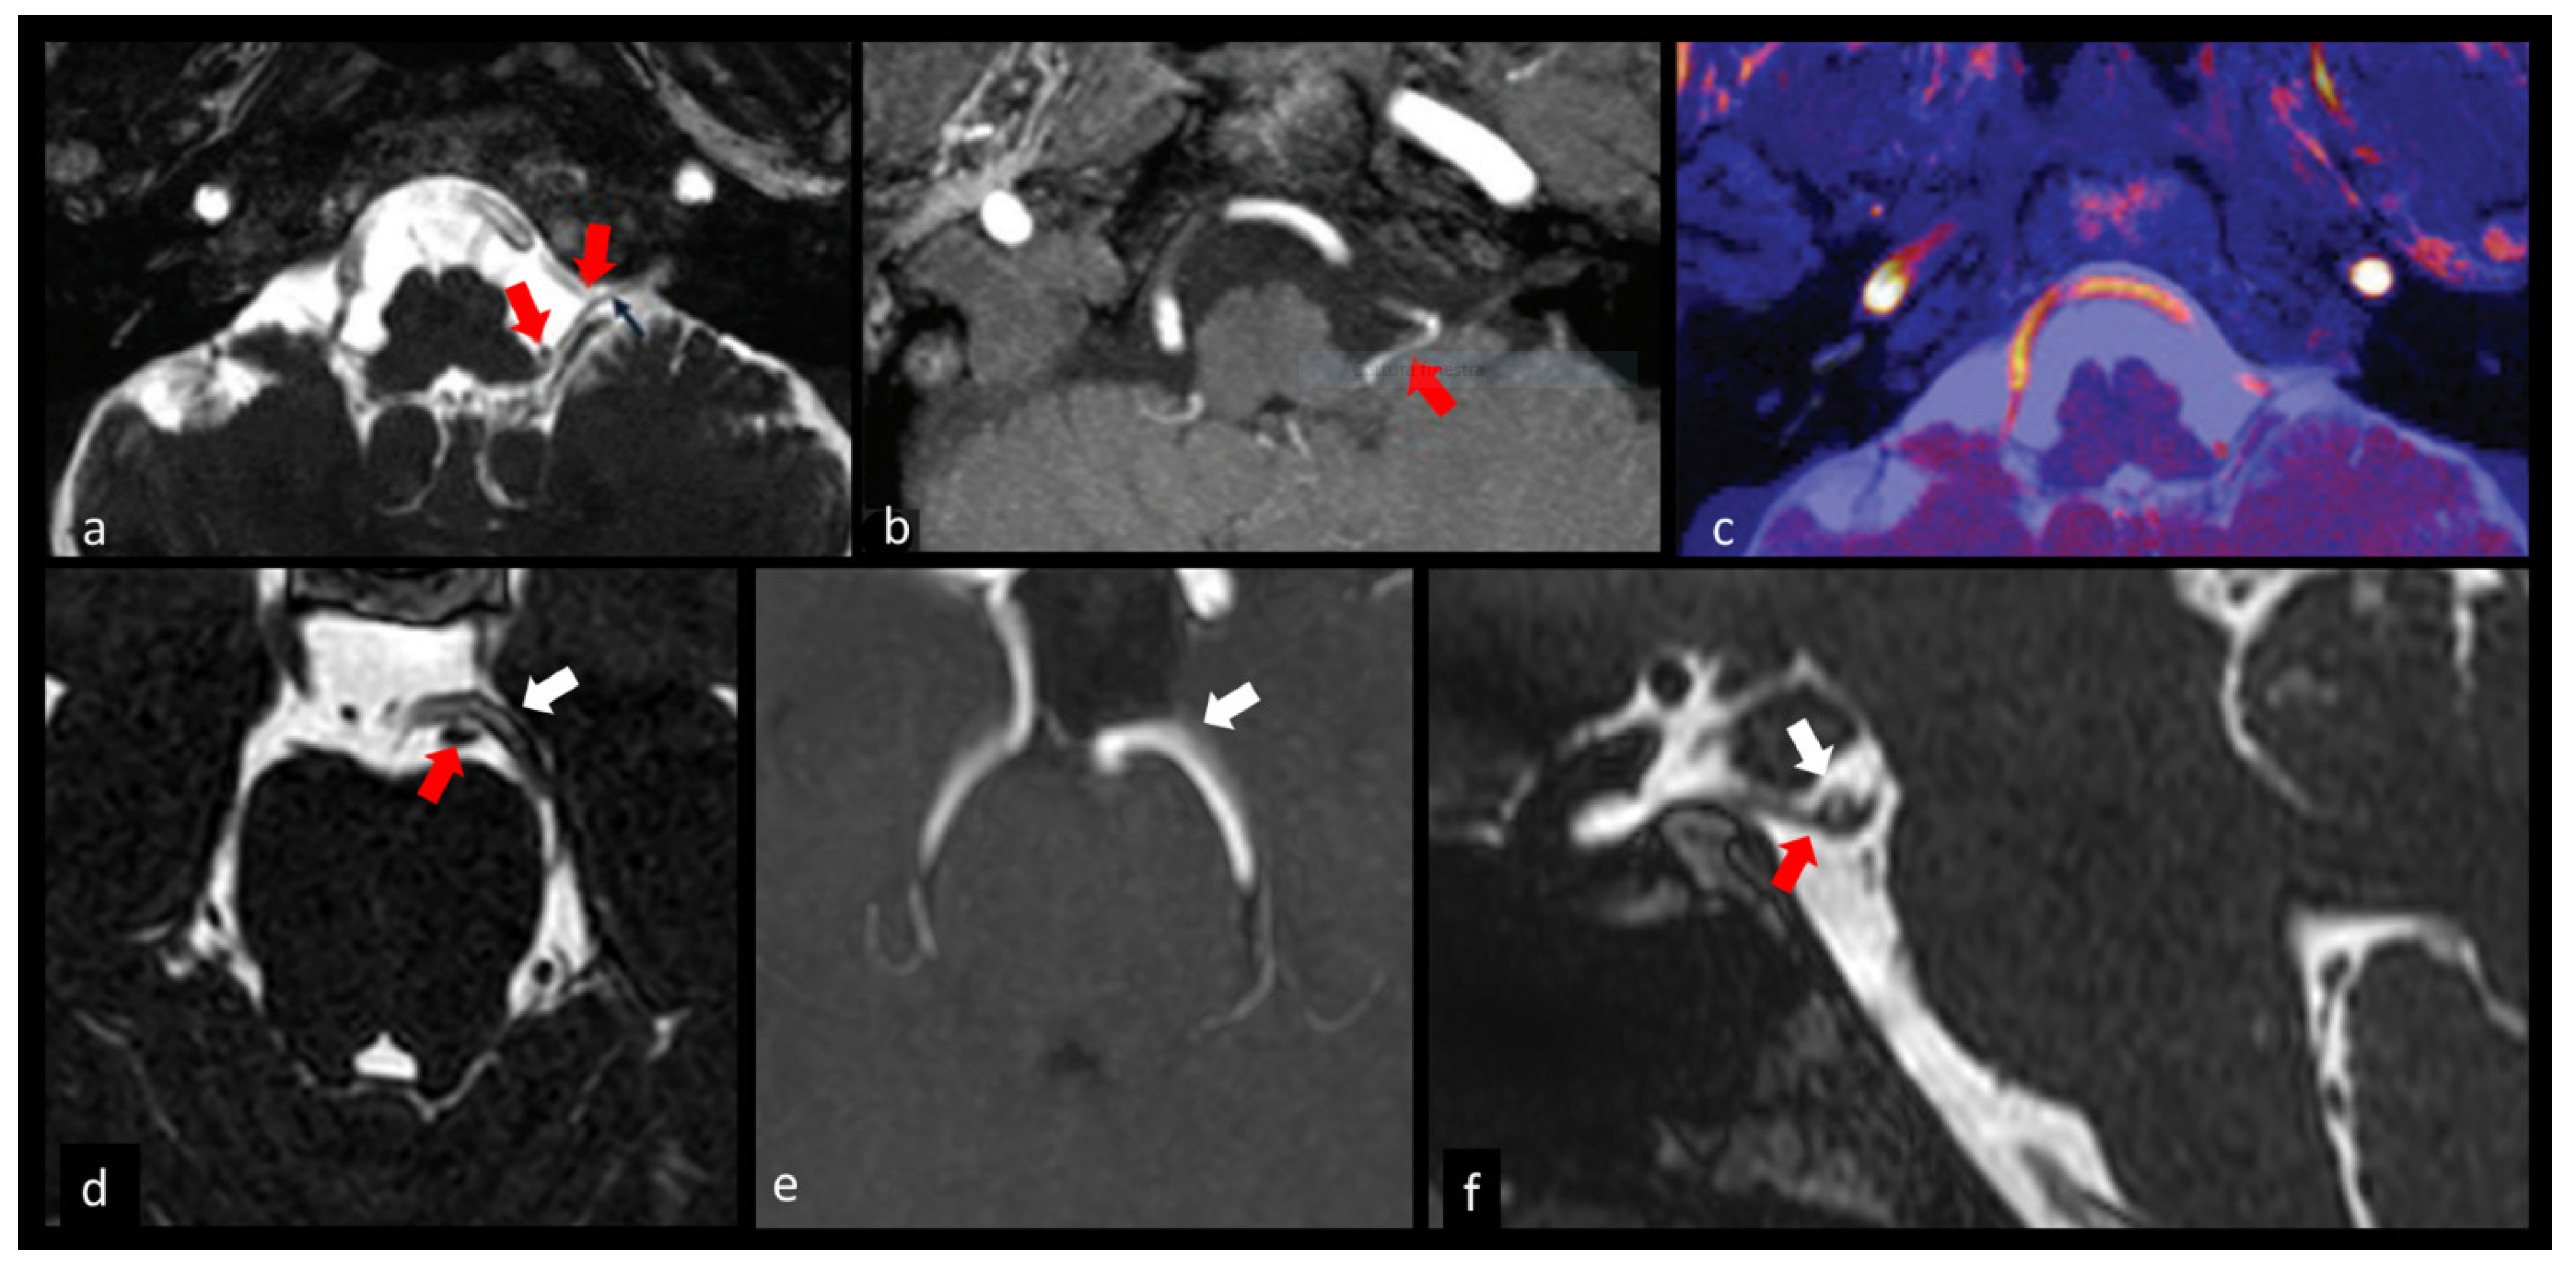

3.1.4. Trigeminal Nerve (V)

3.4. Cerebrovascular Pathology

3.6. Neurocysticercosis